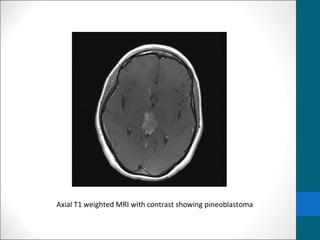

MRI IMAGING

•T1 - isointense to hypointense to adjacent brain

•T2 isointense to adjacent brain

•Areas of cyst formation or necrosis my be present

•T1 C+ (Gd) - vivid heterogeneous enhancement

Axial T1 weighted MRI with contrast showing pineoblastoma

Axial T1 weightedMRI with contrast showing pineoblastoma